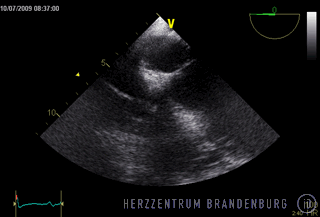

Im Rahmen der Behandlung ist es zunächst wichtig festzustellen wie ausgedehnt eine Infektion fortgeschritten ist. In der Regel ist dazu eine transösophageale Echokardiographie notwendig, um das Ausmaß und die Größe von Vegetationen festzustellen und eine eventuelle Klappenmitbeteiligung einschätzen zu können. Das weitere Vorgehen muss danach individuell, meist in enger Kooperation zwischen interventioneller Kardiologie und Herzchirurgie festgelegt werden.